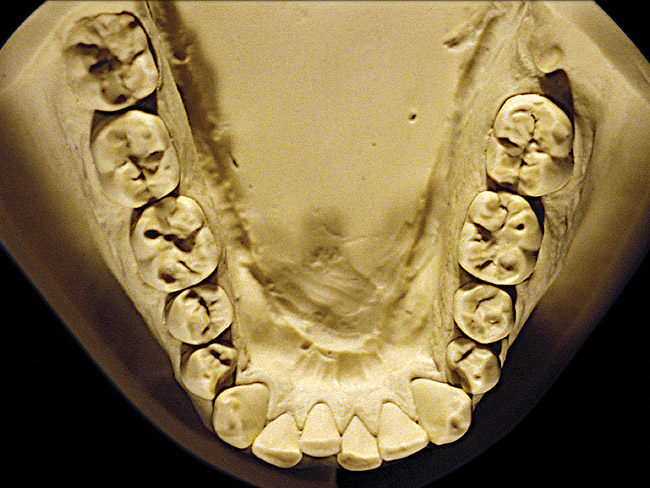

The patient shown in Figure 3 and Figure 4 exhibited severe NCLTS from bruxism. Examination of the casts indicated that the NCLTS was progressively greater toward the anterior teeth. Cupping and cratering was not present because there was no secondary cause. Figure 5 and Figure 6 detail another bruxism patient, but to a lesser degree and one with cupping/cratering caused by toothpaste. The cups or craters were not caused from bruxism because the teeth could not touch the bottom of the invaginations. In both featured patients, upon hand-articulating the casts, the NCLTS facets matched up and the diagnosis of bruxism was confirmed.

Figure 2  Advanced NCLTS from bruxism, mandibular arch.

Figure 2